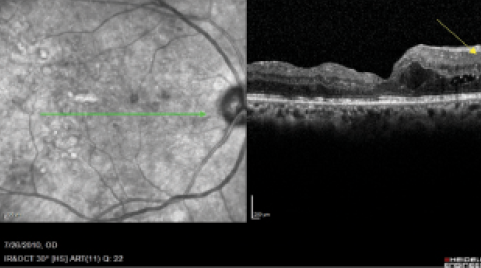

Figure 2. Technician observes pathology running past the captured area and expands to 9-mm scan line, thereby capturing the entire width of the cSLO image.

Occasionally there is pathology that extends beyond the central macula (Figure 1). When the macular pathology runs off the screen, I have taught my technicians to change the width of the raster scan in real time to image the entire area (Figure 2). Lesions or pathology in the midperiphery, temporal macula, or nasal areas can also be imaged easily, thanks to longer-width raster scans, real-time fundus imaging, and optional fixation choices.